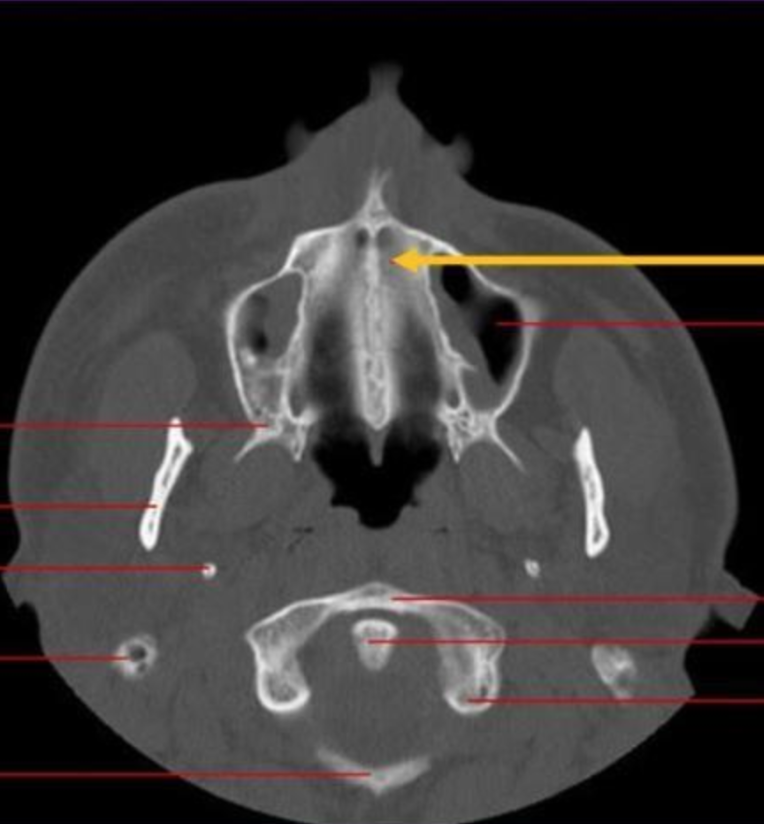

nasopalatine canal

identify the structure indicated by the ARROW